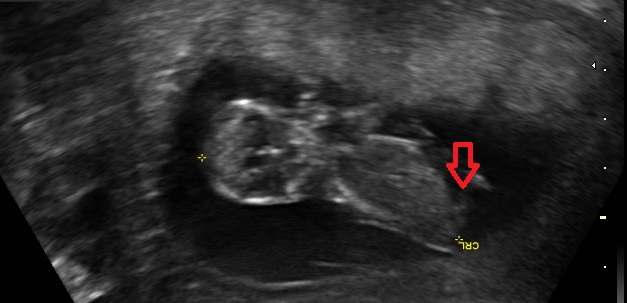

I was 11w5d when I had the scan, although I was measuring 12w1d. I know it's still pretty early, but am wondering if you see anything on these (terrible quality) scan pics! Attachment 23572Attachment 23571Attachment 23573Attachment 23574Attachment 23575